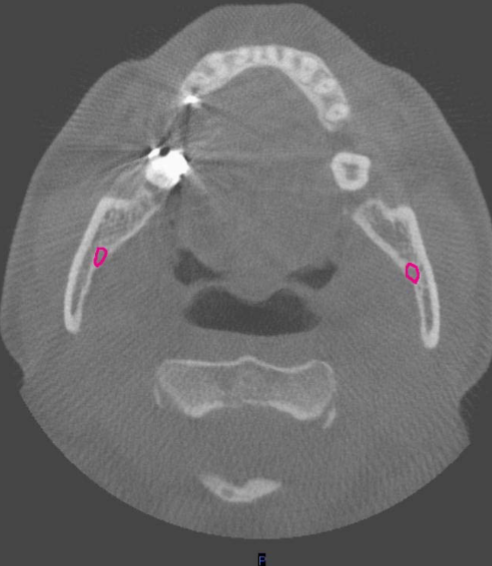

axial

what plane is this

level of maxilla (above maxillary teeth)

at what level is this

mandibular condyle

what structure is this